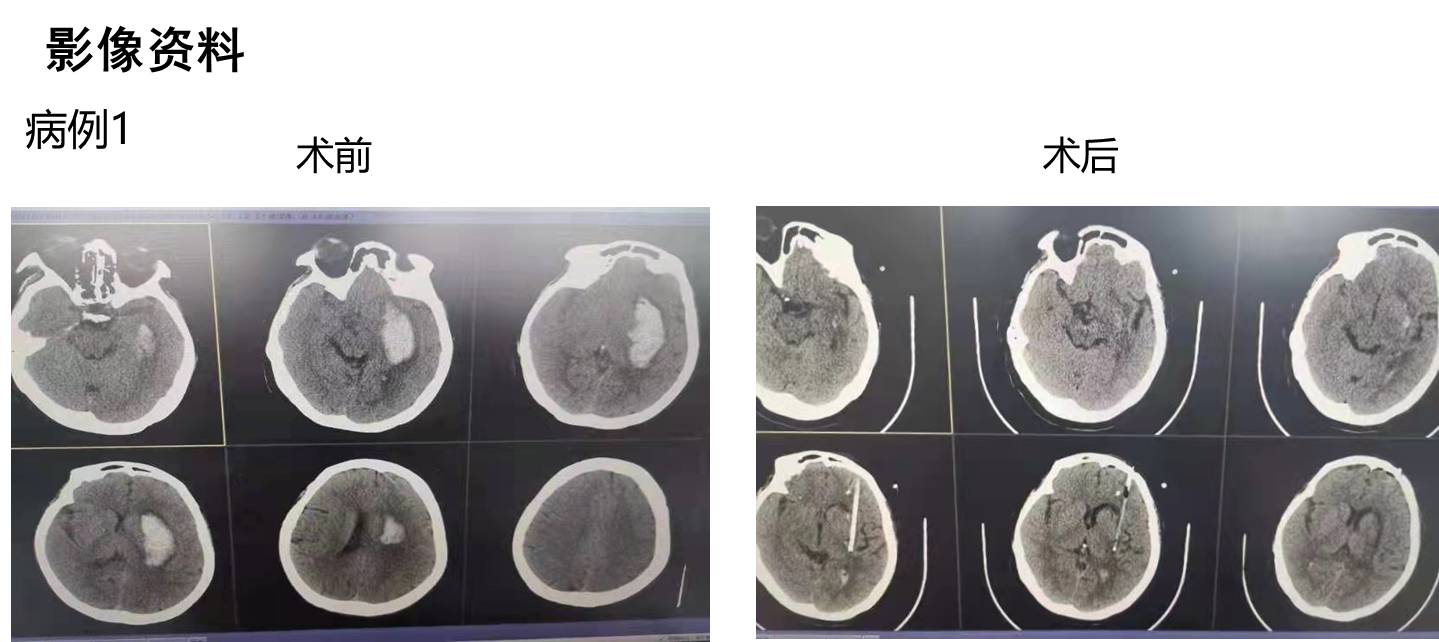

病例术前术后影像:

新型内窥镜技术可实现血肿清除手术全程可视化,包括血肿穿刺、血肿清除及血肿腔内精准电凝止血,手术切口长2.5cm,仅需单一直径1cm骨孔,镜体工作通道外径小于7mm,手术在全内镜内操作,十分微创,血肿部位的深浅在新内镜手术中无难度差别,新型内窥镜血中可视能力,不但可以在全程清晰可视下一次性清除绝大部分血肿,而且还可在有明显出血的血肿腔内轻易找到出血点并进行精准电凝止血,基于新型内窥镜所具有的颠覆性功能,有理由预判脑出血治疗的一些尚没有结论的重要问题的结果。